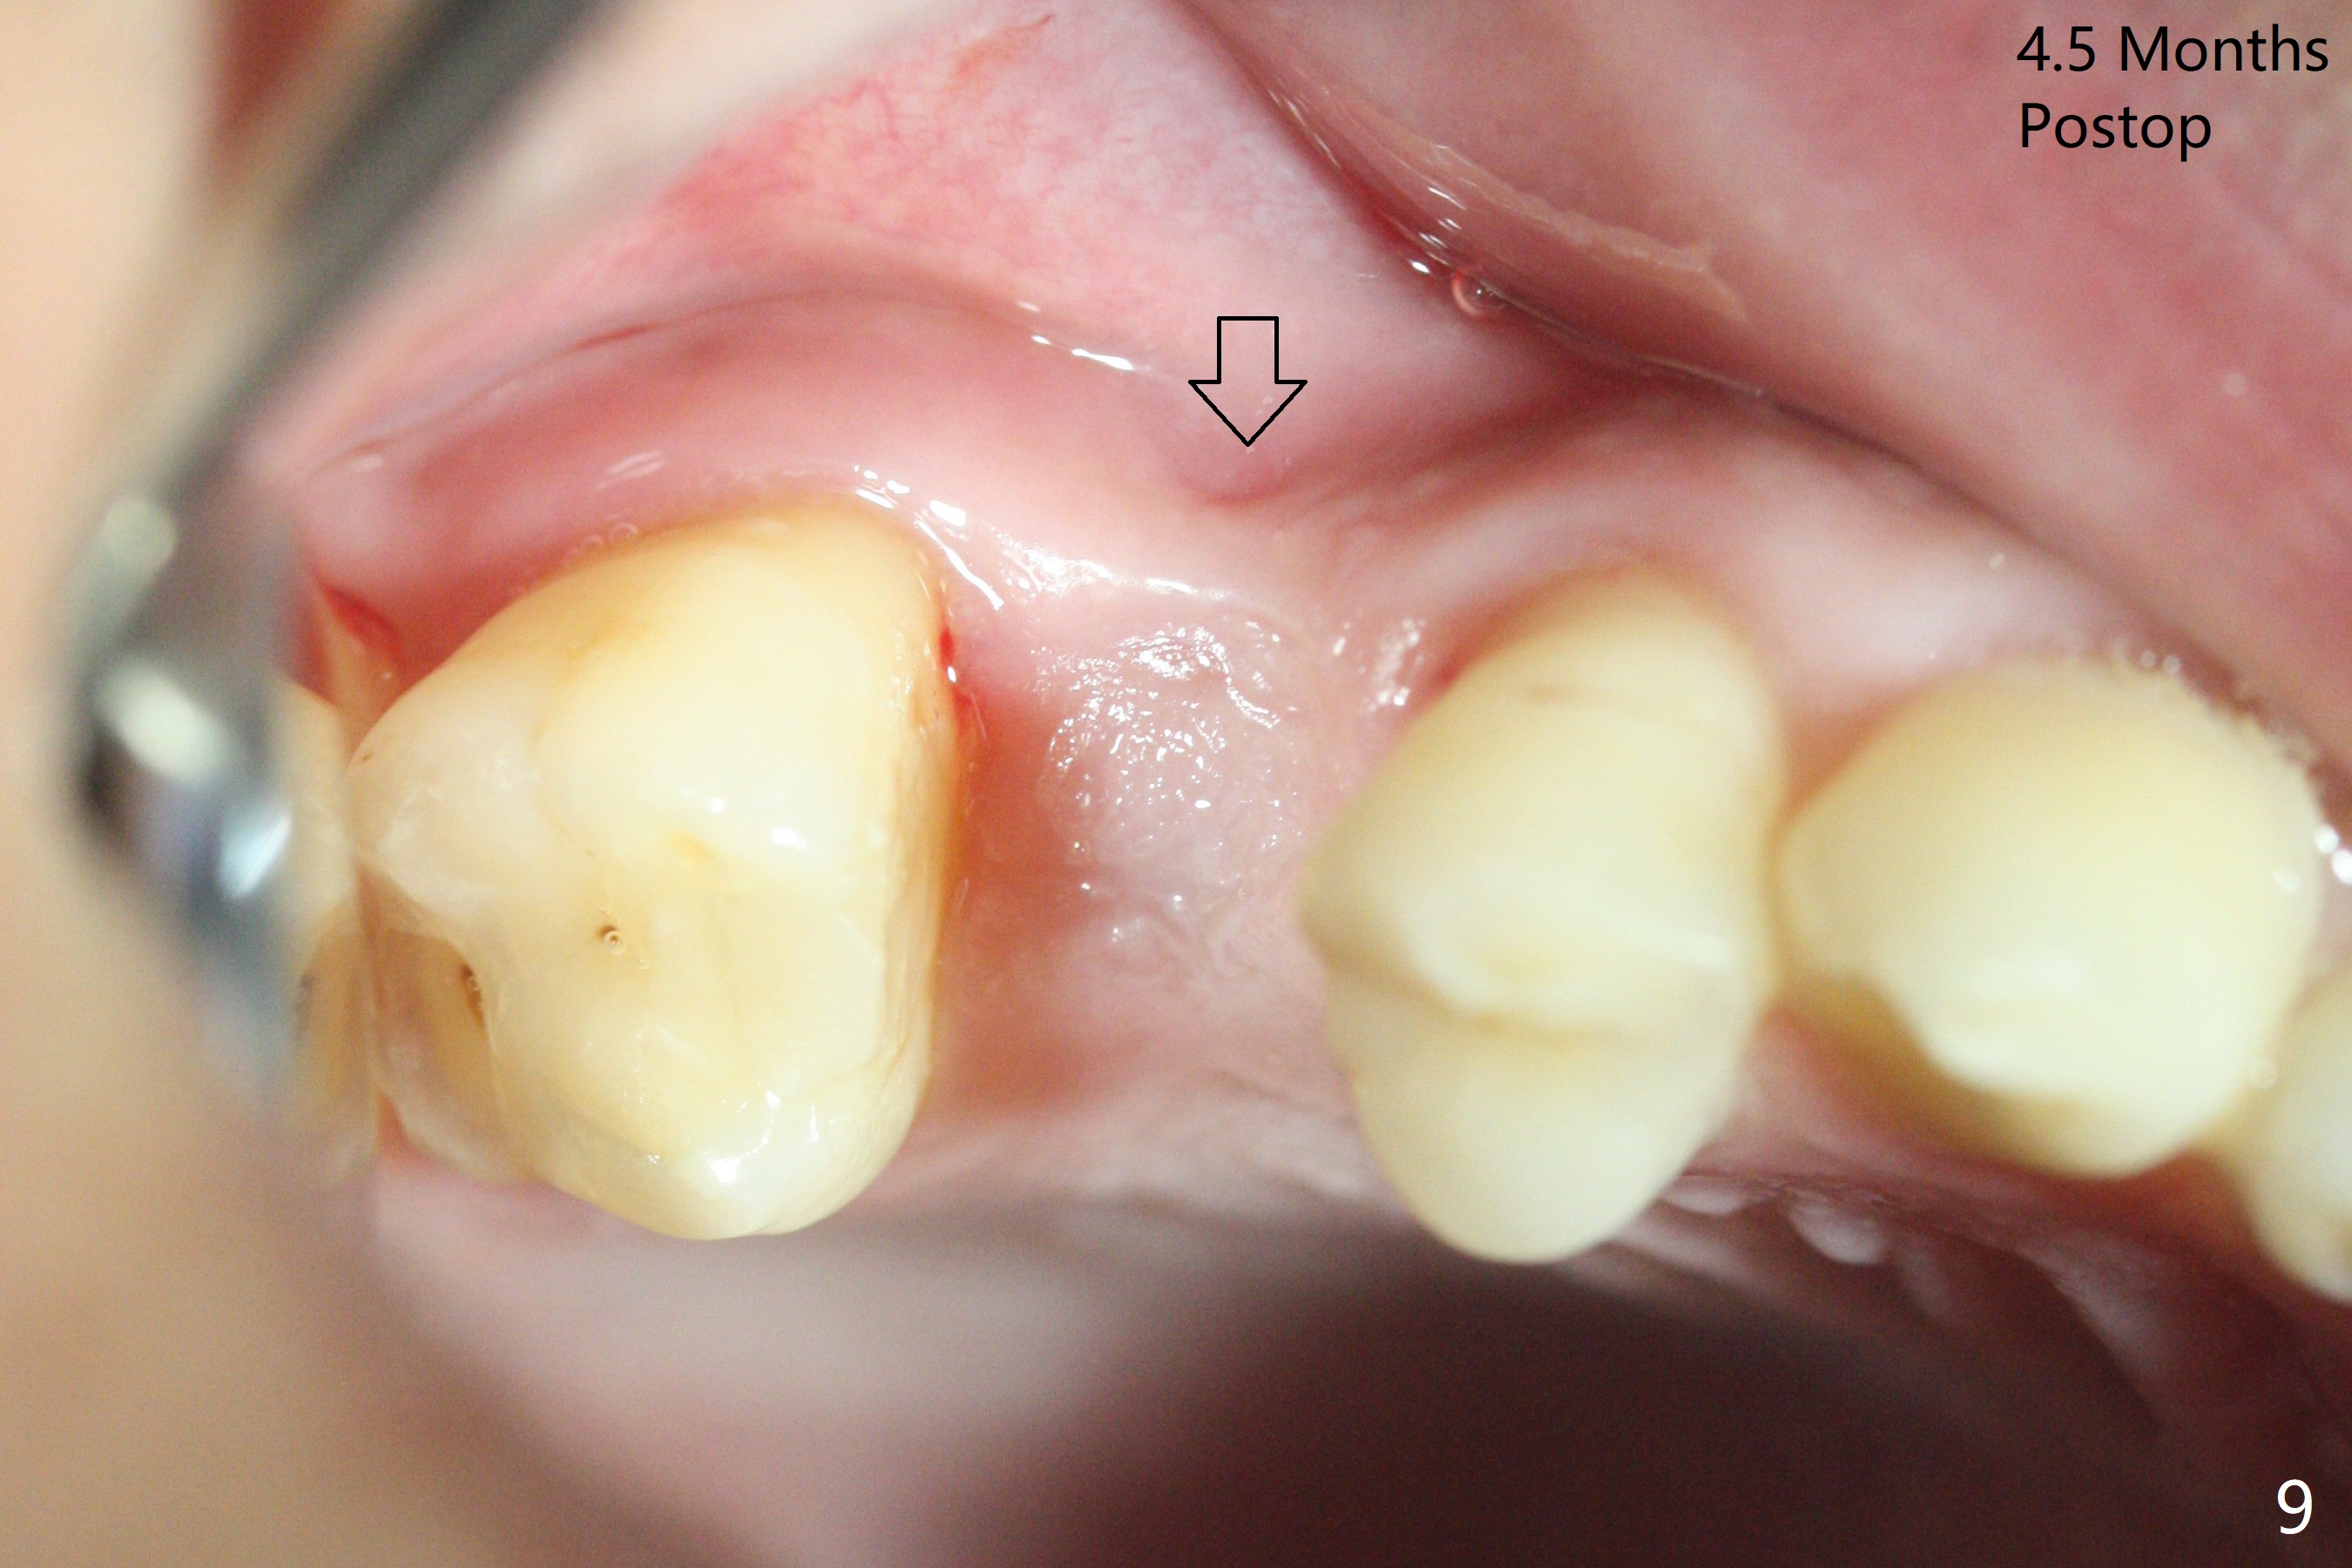

尽管没有任何症状,右上5牙冠粘固后2年5个月,牙冠与基台取出(没有使用扳手,说明基台未完全就位),切开,去除少量肉芽组织,仍然发现植体螺纹暴露(图一),使用一种叫I Brush 钛合金刷子清洁后,放置粘性骨块(图二: S),它坐在牙槽嵴上仿佛非常安稳,多么象马鞍(Saddle)。覆盖一张PRF膜和一小张Cytoplast(不可吸收膜,Osteogenics (company) 图三:箭头),使用PTFE缝线(与Cytoplast同样一种材料)缝合。术后即刻根尖片显示骨粉服服帖帖地坐落在植体和牙槽嵴上(图四:*)。最后覆盖牙周敷料。后者术后十天左右脱落,伤口愈合正常,颊侧瘘道仿佛消失,颊侧骨壁好像不再凹陷了(图五,六)。术后5周,膜已经脱落,缝线撤除后,伤口好像二期愈合,但愿肉芽组织下面骨粉尚未损失太多。术后三个月根尖片显示骨粉减少(图八)。不可吸收膜脱落可能造成骨粉流失。应该做减张缝合。术后4.5个月颊侧骨壁又凹陷(图九:箭头,需要decortication),但是uncover时植体周围都有骨质包绕,术后咬翼片也证明近中,远中骨质接触植体(图十:由于找不到合适愈合基台,直接放置基台和牙冠)。粘固后2.5个月虽然颊侧骨板凹陷,但是没有植体周围炎迹象(图十一)。